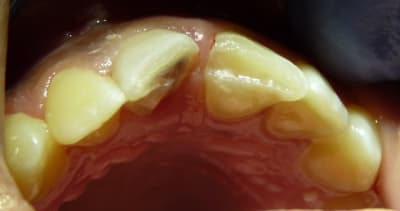

Ici les fractures sont relativement étendues, toute la longueur du bord incisal est perdue.

Même si la dent reste asymptomatique, comment reconstituer ces dents durablement sur le plan fonctionnel et esthétique ?

Patiente revue :

- Dents toujours sensibles (10j après trauma) au froid malgré le CVI.

- 11 s'est colorée (rose : "hémorragie endodontique").

J'ai tenu compte de tes conseils Céramik : j'ai juste fait un collage, sans interposer de matériau.

Je n'ai fait un biseau qu'en vestibulaire : j'aurai du biseauter en palatin aussi pour augmenter la surface de collage.

La patiente est en classe II, ses incisives n'assurent aucun guidage.

J'ai encore beaucoup de mal à faire des compos sur incisives centrales... Le résultat est assez moche, je manque d'expérience.

La patiente et sa maman sont ravies. Je leur ai expliqué que c'était une indication de facettes.